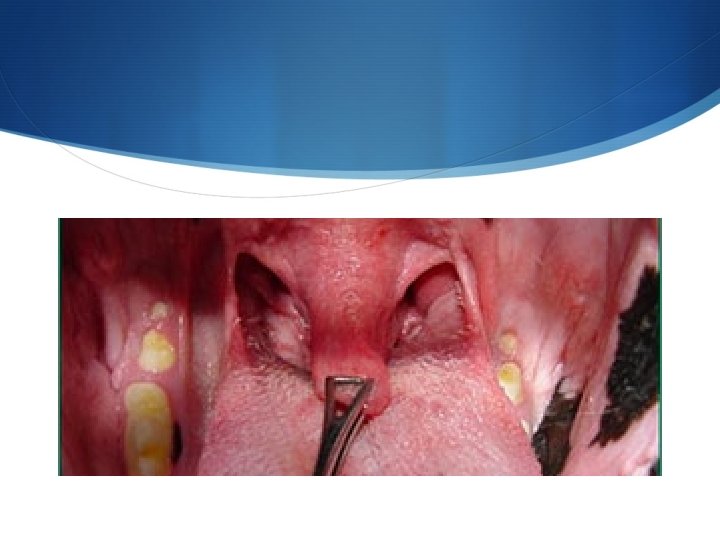

S I soggetti con questa sindrome possono essere portatori di anomalie congenite come stenosi delle narici, allungamento del palato molle eversione dei sacculi laringei ed ipoplasia tracheale.

S I soggetti con questa sindrome possono essere portatori di anomalie congenite come stenosi delle narici allungamento del palato molle eversione dei sacculi laringei ed ipoplasia tracheale (filmati 1 e 2).